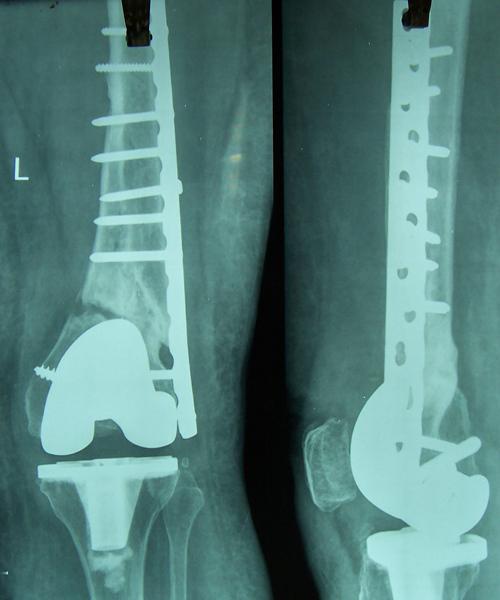

Case:14 Periprosthetic Fracture

60 years old patient with total knee replacement on left knee presented with open grade 1 injury. Debridement & slab given on emergency bases. Fixation with plate & screws done. Union was seen after 6 months.

Pre-Op AP

Pre-Op Lat.

Immdiate Post-op

1 and half months Post-op

2 and half months Post-op

3 and half months Post-op

4 and half months Lateral

6 Years Follow-Up